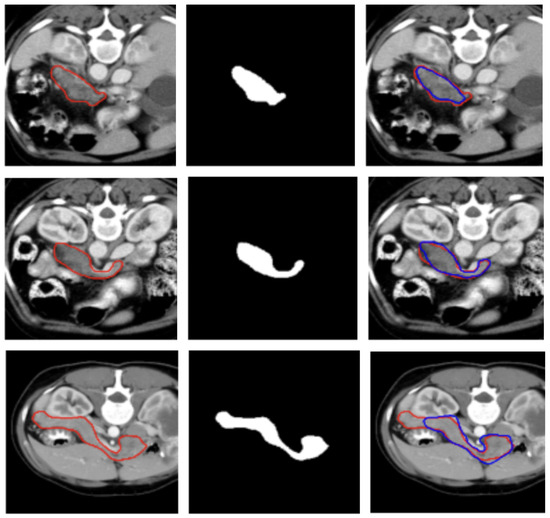

Machine learning, especially deep learning, has become prevalent in medical imaging analysis to assist in the detection, diagnosis, and treatment of various diseases. Despite the success of deep learning in medical imaging analysis, the main bottleneck in medical imaging analysis is the lack of large-sized and properly annotated datasets, which are very costly to establish. Recently, many studies have attempted to use various mathematical models to improve deep learning to address this challenge. In particular, semi-supervised, self-supervised, and unsupervised deep learning algorithms have showed promising results in medical imaging analyses, including image registration, detection, classification, and segmentation. Papers focused on using novel machine learning algorithms to solve problems in medical imaging analysis are welcome to be submitted to this Special Issue.